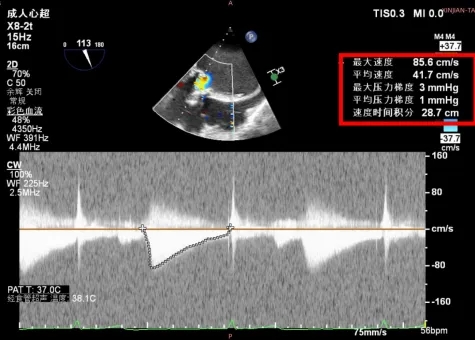

康复大学青岛中心医院林明山教授分享一例“双瓣一站式”高难度VIV病例,深刻展现自膨短瓣在生物瓣衰败VIV中的应用价值。患者83岁男性,于2010年行主动脉瓣置换术、二尖瓣置换术及三尖瓣成形术,现主动脉瓣和二尖瓣生物瓣均出现重度反流,术前超声/CT充分评估后,决定采用经心尖入路,先行主动脉瓣瓣中瓣植入术(TAVR-VIV),顺利送入ScienCrown TAVTA 23mm瓣膜,得益于该款瓣膜短瓣架设计,完全释放后对血流影响小,因此TAVR-VIV术中无需起搏,瓣膜初次释放位置稍浅,部分回收调整瓣膜深度重新释放,即刻造影示瓣膜位置良好,无张力脱钩瓣膜位置稳定,术后TEE示主动脉瓣平均跨瓣压差仅4mmHg。随后行二尖瓣瓣中瓣植入术(TMVR-VIV),经心尖入路植入ScienCrown TAVTF 29mm瓣膜,主动脉根部造影,冠脉显影良好无瓣周漏,术后TEE示二尖瓣平均跨瓣压差仅1mmHg。

TAVR-VIV术后TEE